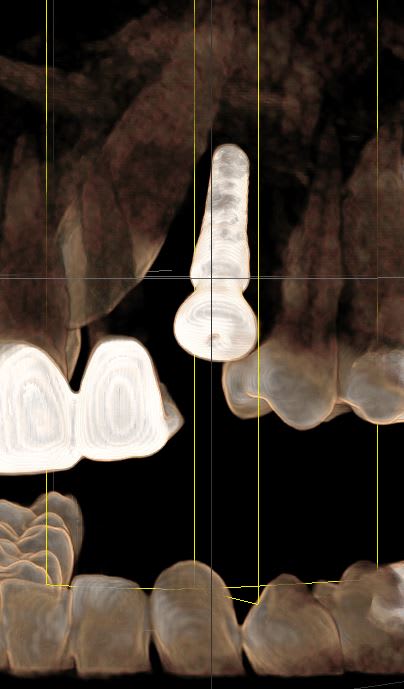

Voici les images. Celui entre les dents je me dis que peu d'os était dispo mais pour l'autre, je suis emmerdé, je n'ai pas d'explication mais je n'ai pas de radio. L'os était D2 pour la 46 mais pas d'image de l'implant , juste celle du guide.

Bref, comment vous fonctionnez avec guide? Forets irrigation interne?